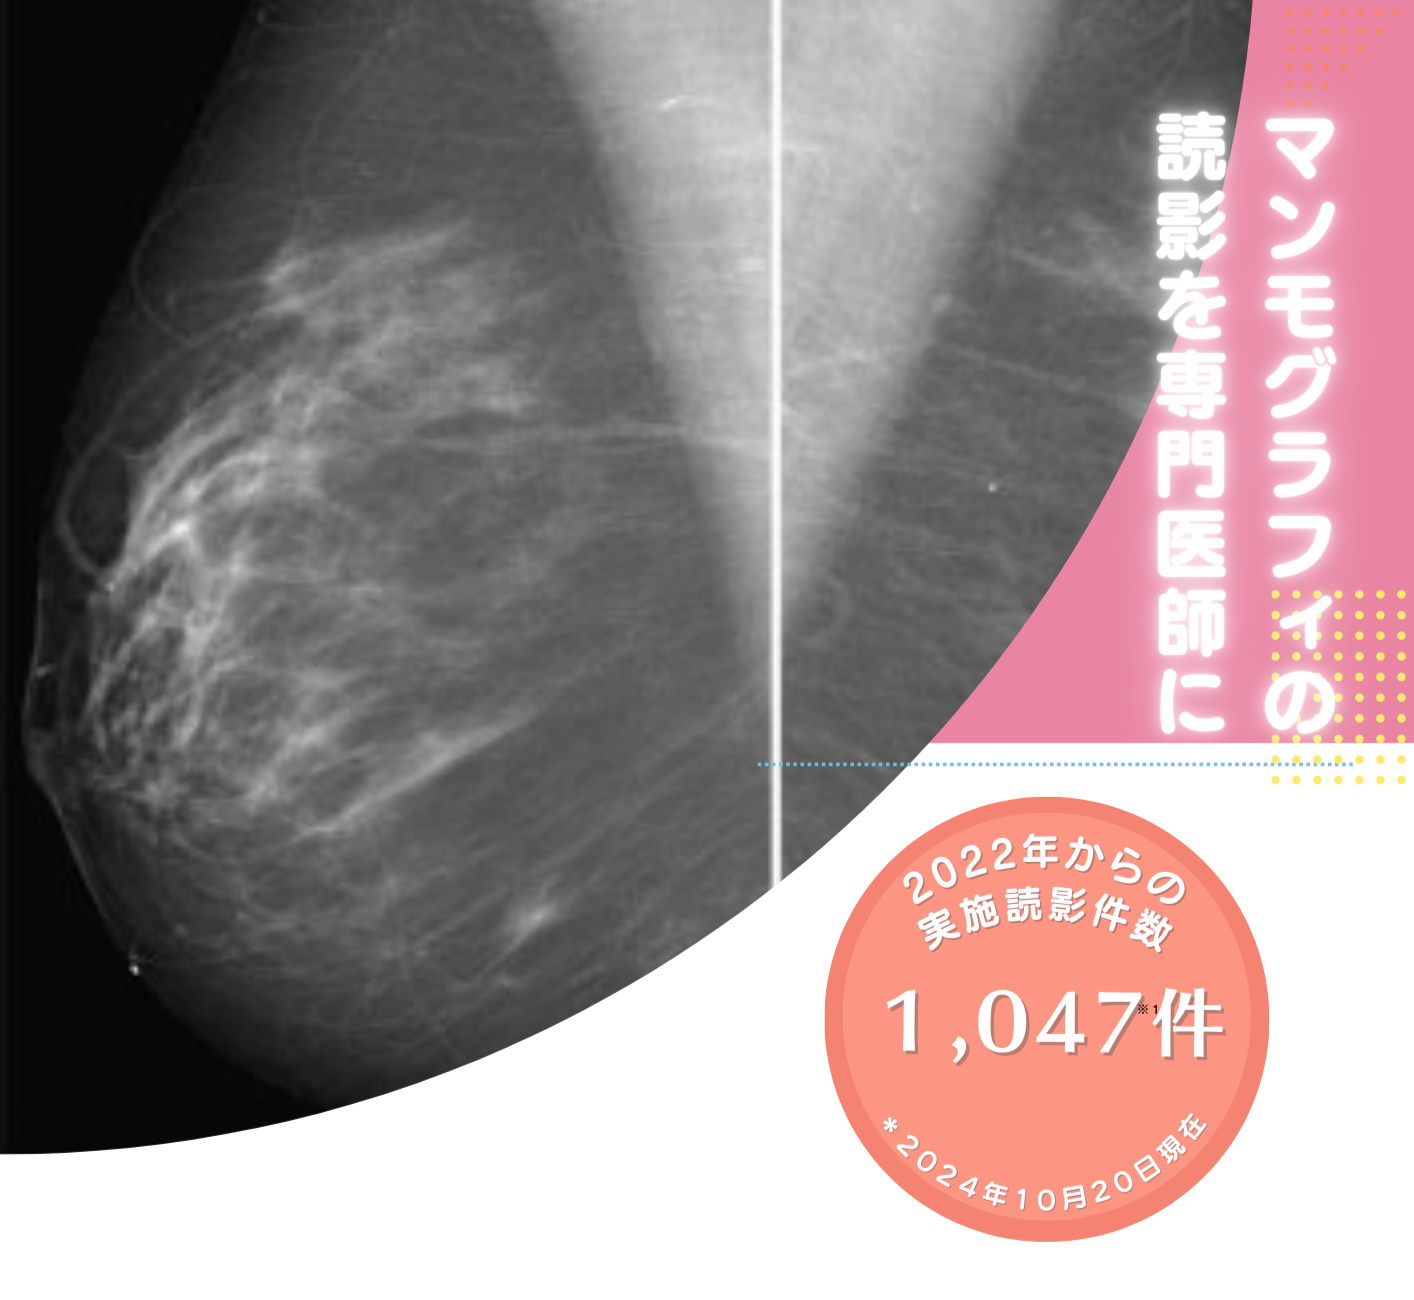

マンモグラフィ画像読影協力

マンモグラフィの読影業務を委託したい医療機関さまのお手伝いをさせていただきます。検診マンモグラフィ読影認定医師による読影を行っております。入会金などはいただきません。

質の高いマンモグラフィ読影で安心をお届けします。

私たちのマンモグラフィ読影サービスでは、最新の技術と経験豊富な専門家による正確な診断を提供します。